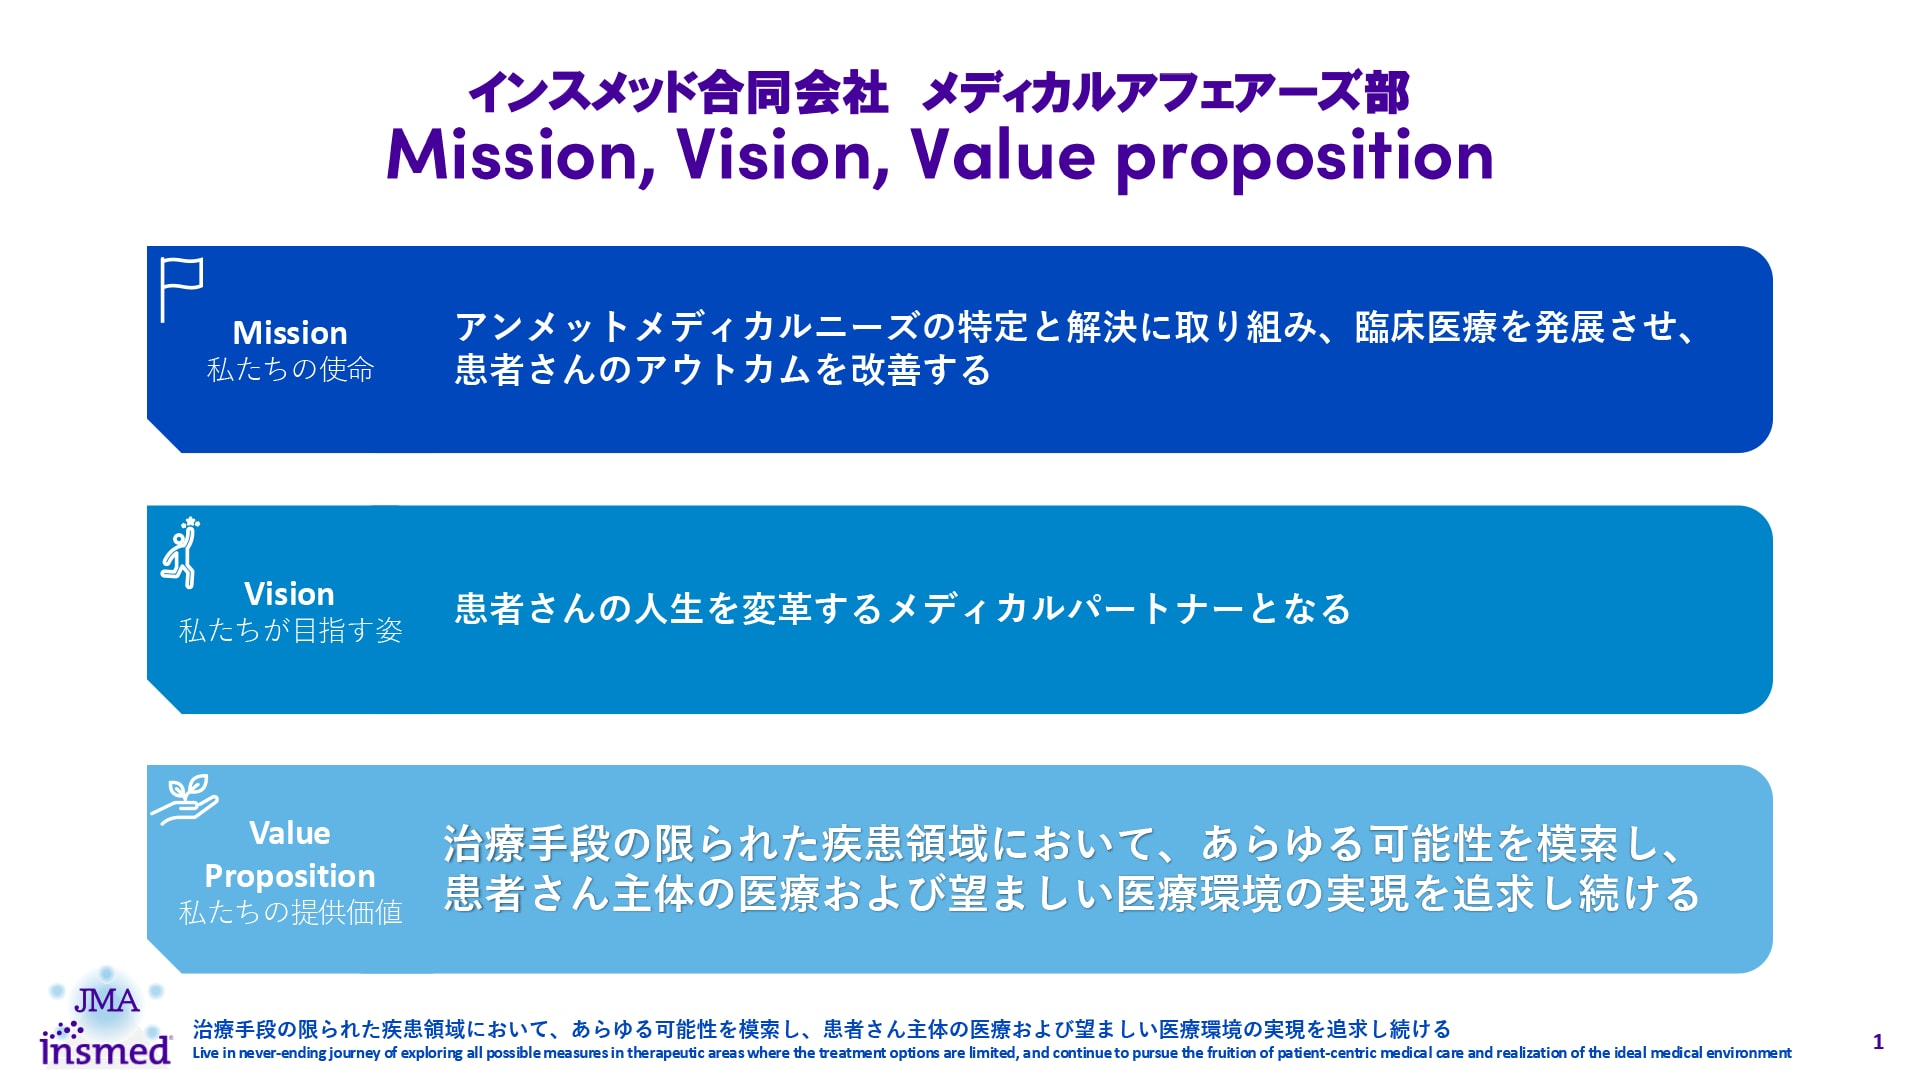

気管支拡張症は、不可逆的に進行する慢性炎症性疾患であり、近年世界的に有病率の増加が示唆され注目が集まっています。

本サイトは気管支拡張症を詳細に解説することで、医療従事者の方々のこの疾患の認知・理解を高め、適切な医療・ケアに活かしていただく目的で開設いたしました。